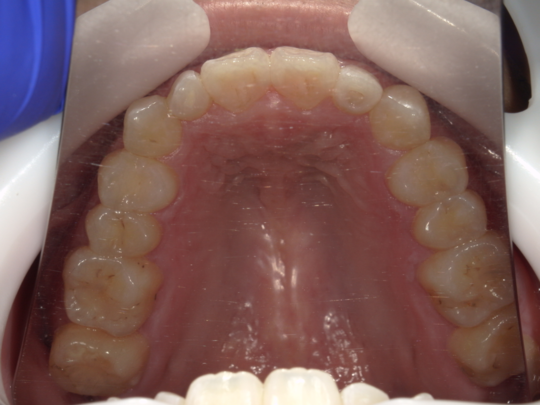

実例写真①

矯正前(上の歯)

矯正後(上の歯)

矯正前(下の歯)

矯正後(下の歯)

こちらの患者さまは、あごが小さいために前歯がきれいに並びきらず、「叢生(そうせい)」という前後がデコボコな歯並びでした。矯正後は、きれいに前歯が並んだだけではなく、上下の噛み合せも正しい位置に動き、しっかりと噛めるようになりました。

治療説明 歯科矯正でも目立ちにくい矯正方法です。透明に近いマウスピース型の矯正装置(アライナー)のため、歯に装着しても目立つことなく歯並びを矯正することが出来ます。また、一人ひとりの合わせて矯正装置を作製いたします。

治療期間 11か月

治療費用498000 円

治療の副作用(リスク)歯の動き方には個人差があり、予想された治療期間が延長する可能性があります。治療中は矯正歯科装置をつけるためハミガキを適切に行ってお口の中を常に清潔に保ち、さらに、かかりつけ歯科医に定期的に受診することが大切です。マウスピースの使用状況、定期的な通院など、矯正歯科治療には患者さんの協力が必要であり、それらが治療結果や治療期間に影響します。治療の経過によっては当初予定していた治療計画を変更する可能性があります。保定装置の装着時間が十分確保できない場合、歯並びや、咬み合せの「後戻り」が生じる可能性があります